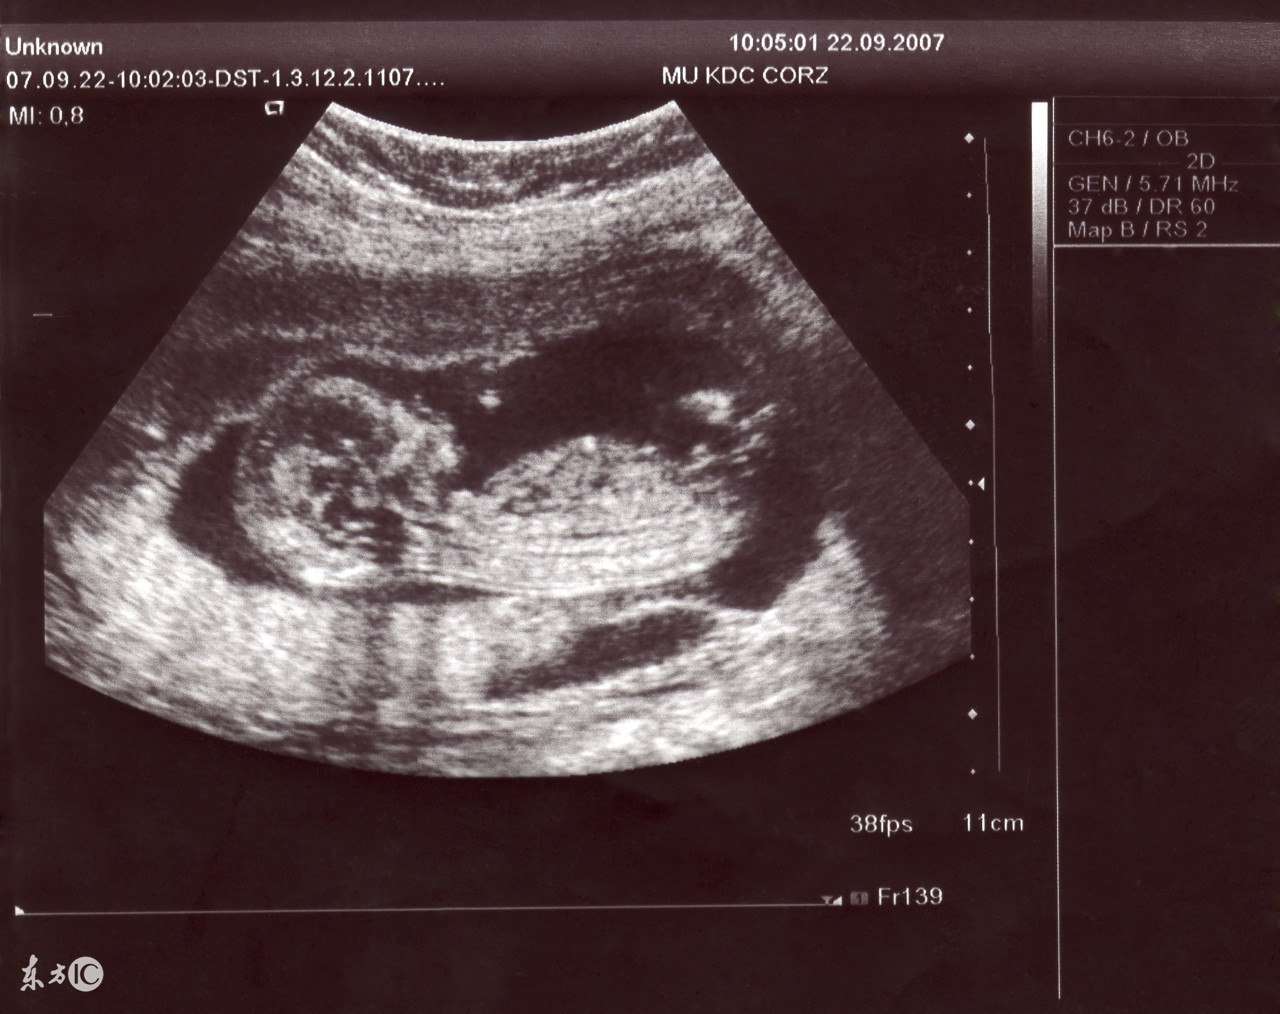

这个月的产前检查要做B超,以了解胎儿的大小、活动情况、心跳、羊水量、胎盘位置、器官发育情况等。